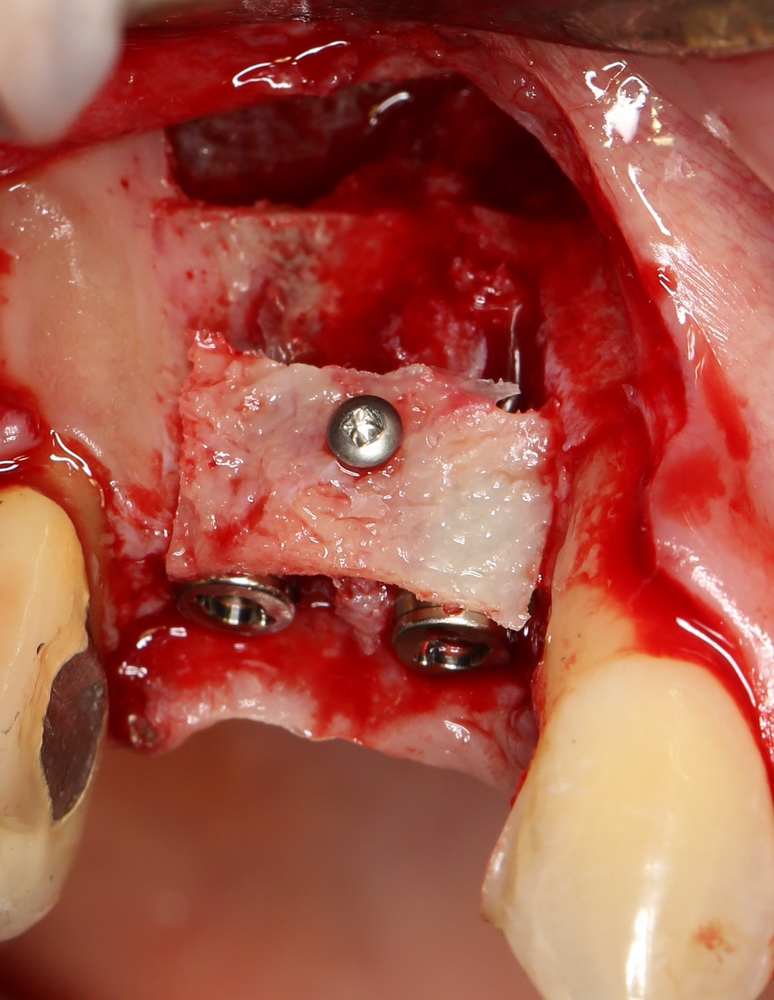

Если получаемый при создании доступа костный фрагмент планируется использовать для остеопластической операции, то площадь окна рассчитывается, исходя из размера этого костного фрагмента. Разумеется, это возможно при адекватной толщине наружной стенки верхнечелюстной полости (рис 30, 31).

Рисунок 30, 31. При сочетании синуслифтинга с остеопластической операцией площадь окна рассчитывается, исходя из размеров необходимого для остеопластики костного фрагмента (слева формирование окна, справа – фиксация костного блока для восстановления объема альвеолярного гребня)